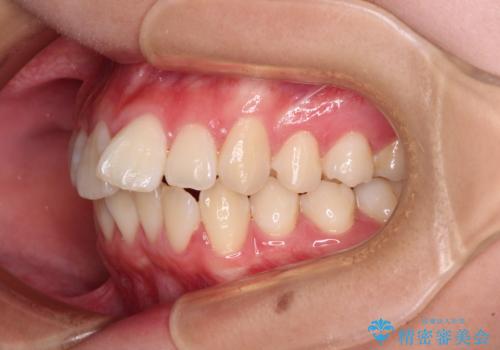

- 前歯がくちばしのように飛び出していることを気にして来院された患者様です。

唇が前方に突出している横顔が気になっているため、上下左右の第一小臼歯4本を抜歯し、ワイヤー装置にて矯正治療を行うこととしました。

わずか2年弱で一気に口元が変化し、患者様には大変満足していただけました。